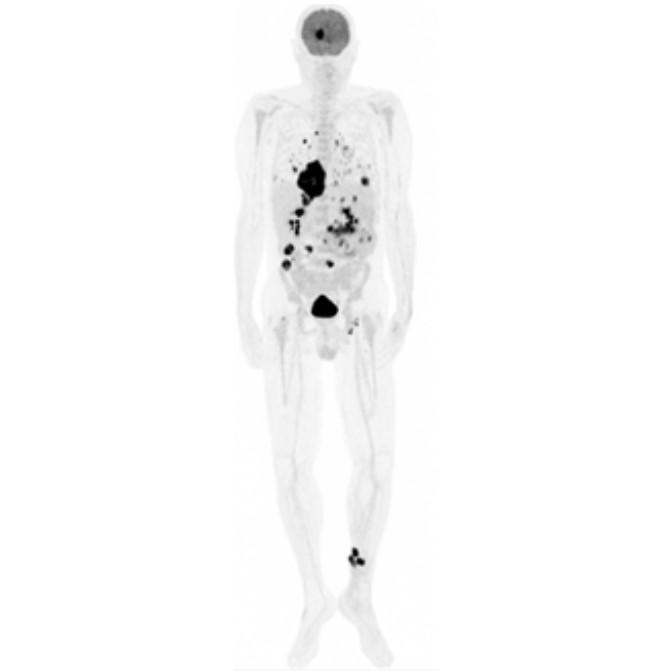

Partial nml and melanoma PET scan